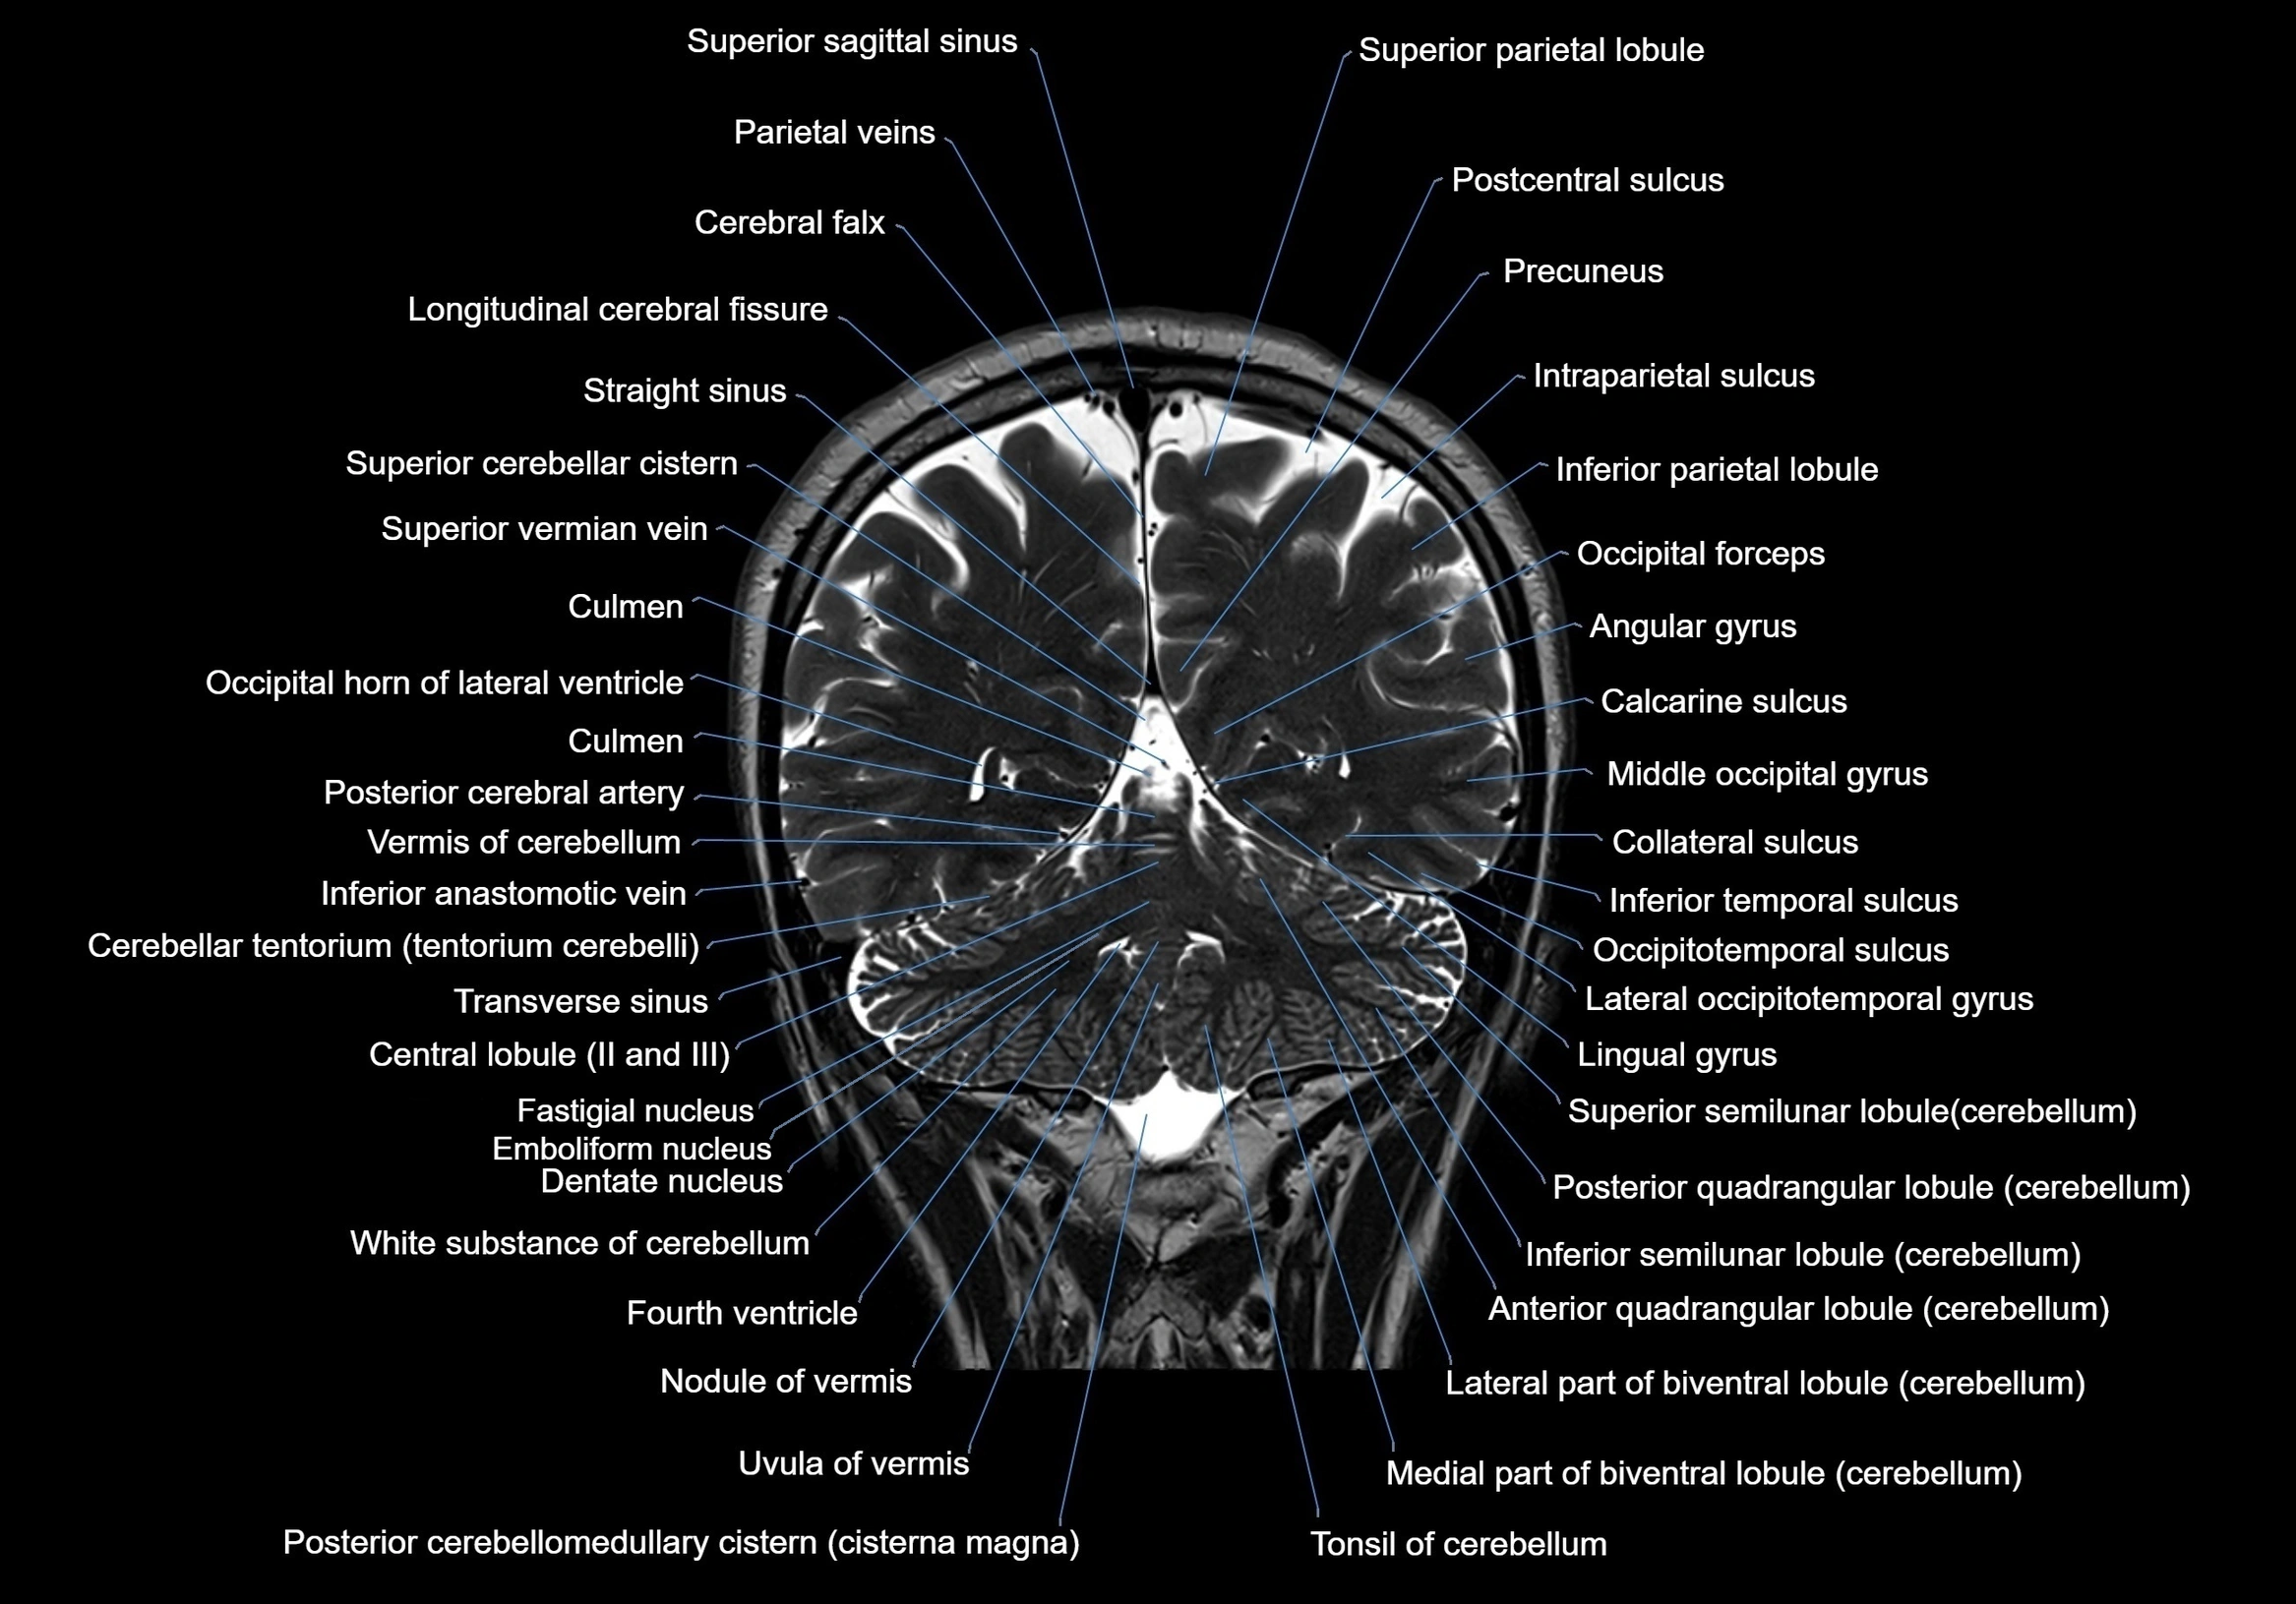

MRI images